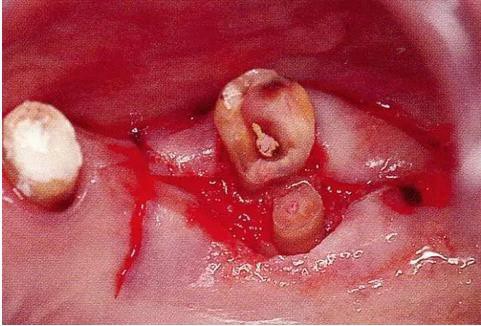

▼圖16-3

圖16-3 對(duì)右上6.7顎側(cè)根的頰側(cè)牙槽中間骨脊缺失進(jìn)行處理,對(duì)應(yīng)高度來對(duì)右上5遠(yuǎn)中牙槽骨進(jìn)行少量切除。之后,對(duì)應(yīng)右上5遠(yuǎn)中牙槽骨的高度對(duì)近中以及右上4的牙槽骨進(jìn)行治療處理。牙槽骨的整體形態(tài)盡可能平坦,沒有極端的段差留下。之后,通過apically positioned flap進(jìn)行縫合固定。結(jié)果就能提高術(shù)后清潔性,得到良好的牙周環(huán)境。